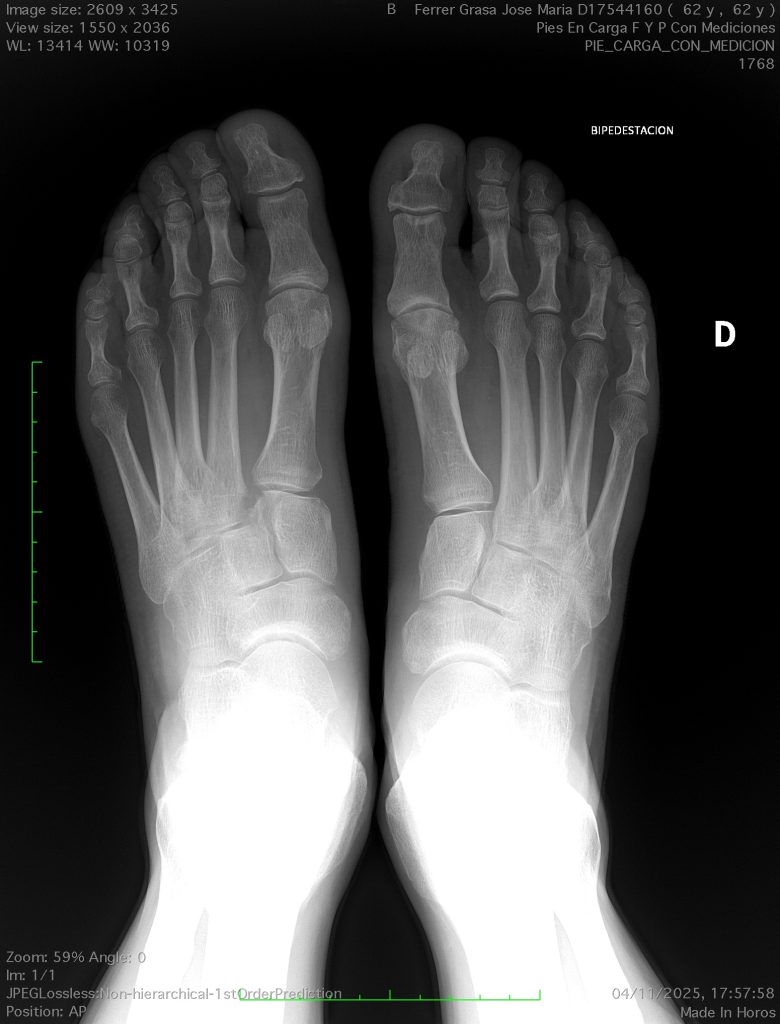

Hallux Valgus (juanetes)

El término juanete se refiere a una hinchazón o prominencia en el lado de la articulación del dedo gordo, que se produce cuando el dedo gordo del pie se desvía demasiado hacia el segundo. El término médico para este problema es hallux valgus.

No todos los hallux valgus son dolorosos y algunas personas pueden tener grandes juanetes sin experimentar dolor significativo. Sin embargo, cuando el dedo gordo del pie se desvía puede causar presión sobre el segundo dedo del pie, dando como resultado un segundo dedo del pie en martillo. En algunos casos, los dos primeros dedos de los pies se cruzan, por lo que es difícil caminar.

De acuerdo con estudios realizados, hasta el 30 por ciento de las personas desarrollarán juanetes en algún momento de sus vidas. Entre las causas más frecuentes por la que se desarrollan los juanetes están las genéticas y la mayoría de las personas con juanetes tiene antecedentes familiares de la enfermedad.

Si una persona es propensa a desarrollar un juanete, el calzado apretado es probable que cause que el dedo gordo del pie se deforme. Este es el motivo por el que esta patología es mucho más común en mujeres que en hombres. El tacón alto y/o los zapatos de puntera estrecha no son la causa principal del problema, pero el calzado puede acelerar la enfermedad.

Otras causas de juanetes incluyen lesiones, la artritis y el desequilibrio muscular.

Para el diagnóstico es necesario realizar una radiografía con el fin de determinar la extensión de la juanete y cualquier artritis asociada.

En algunos casos, zapatos cómodos y anchos pueden ser suficientes para aliviar el dolor, así como plantillas y ortesis. Pero es muy importante para el tratamiento tener en cuenta cualquier anomalía en la biomecánica. Este término se refiere la postura del pie y de la pierna durante el movimiento, por lo que en algunos casos es necesaria la corrección quirúrgica.

Existen diferentes técnicas para la corrección quirúrgica, y esta se debe adaptar a cada caso de forma individual.